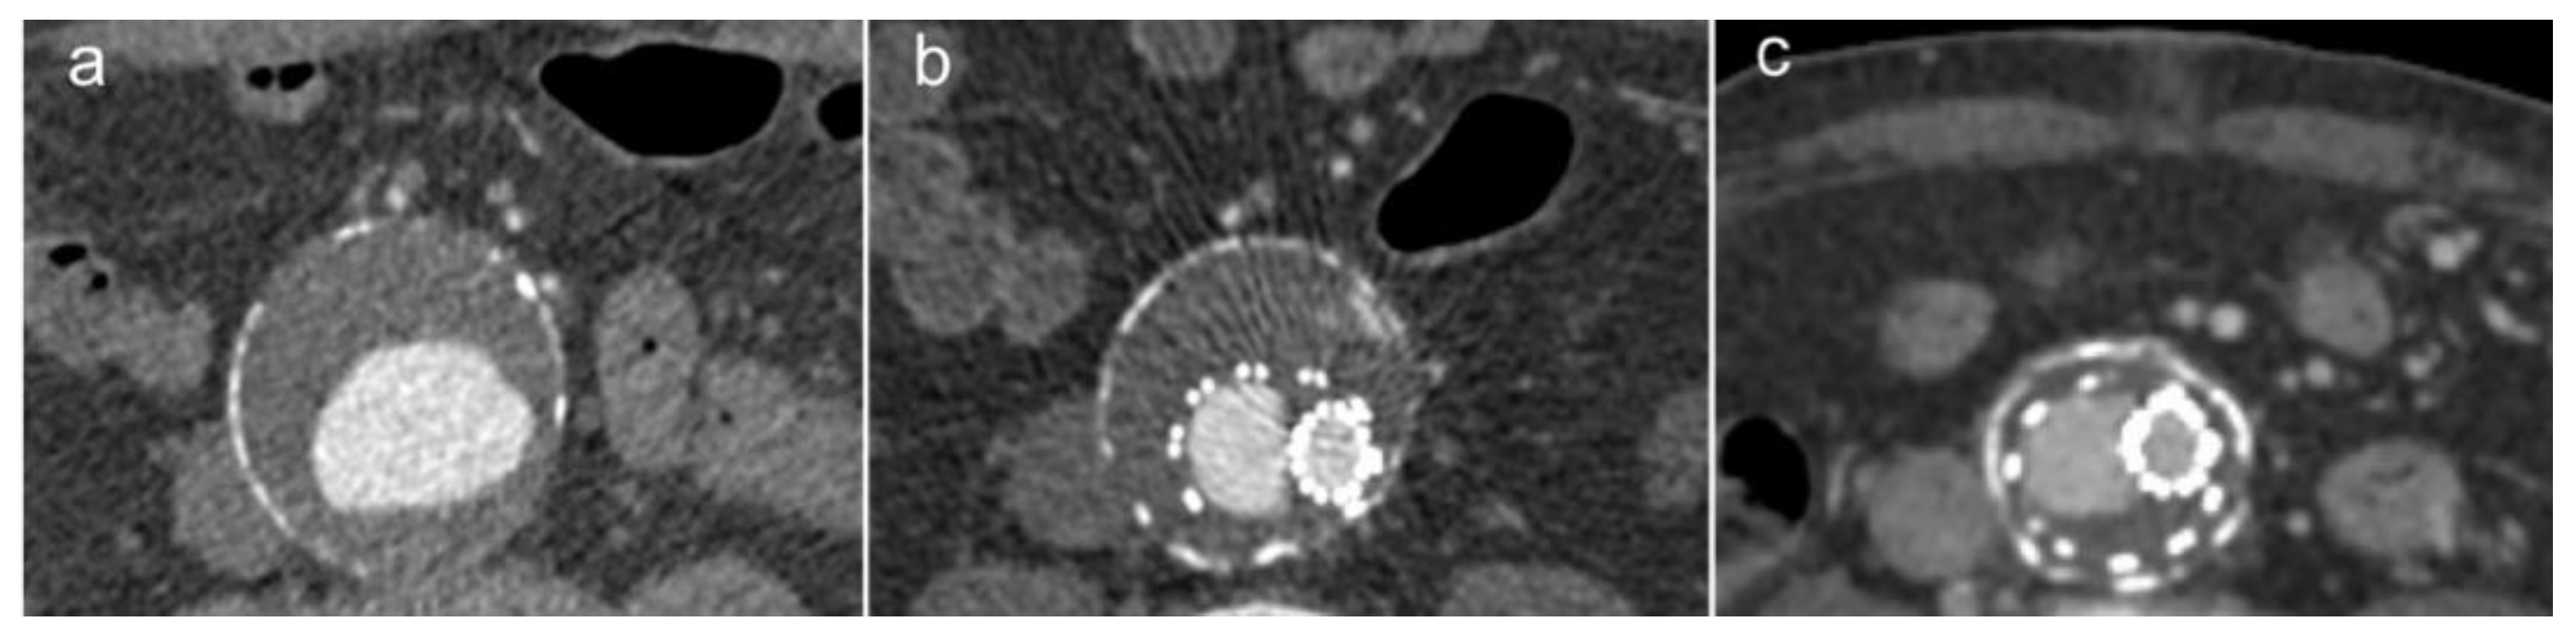

3.1. Chimney EVAR (ChEVAR)

3.3. Endoanchors